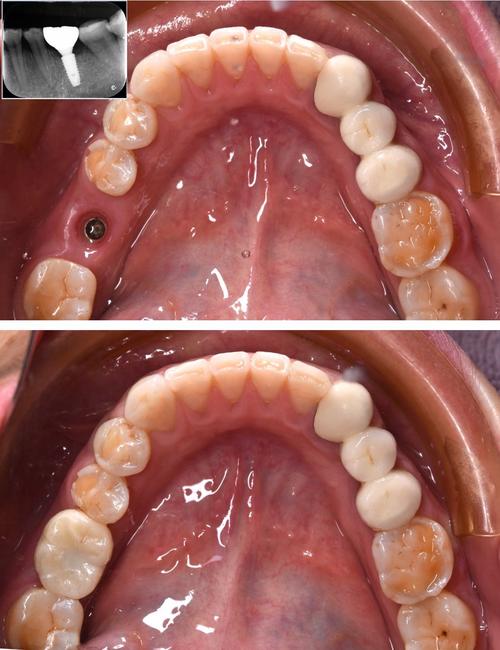

我种的牙用了三年多,从最初的忐忑不安到现在的习以为常,这段经历让我对“牙齿”有了全新的认识,缺牙那几年,我总感觉吃饭不香,连笑都小心翼翼,生怕露出牙缝里的尴尬,后来下定决心种牙,从拍CT、植入种植体到戴上牙冠,整个过程像是一场和牙齿的“重生之旅”,而如今,这颗牙早已成为我生活中不可或缺的一部分,每天陪我咀嚼美食、自信微笑。

等到三个月后复查,医生说种植体和牙骨结合得很好,可以正常吃东西了,我简直像解放了一样,第一次吃排骨时,我试探着用种植牙咬了一小口,居然没松也没疼,那一刻突然有种“失而复得”的喜悦——原来缺牙的痛苦,只有经历过才懂。

现在的种植牙,和旁边的真牙几乎没有区别,咀嚼时力度均匀,咬苹果、啃鸡腿都不在话下,甚至觉得比原来的牙更有“劲儿”(可能是心理作用,但医生说种植体的支持力确实比活动假牙好),不过我也没因此“放飞自我”,坚果壳、螃蟹腿这种硬东西还是坚决不碰,毕竟牙冠是陶瓷的,虽然硬度高,但磕到硬物可能会崩瓷。